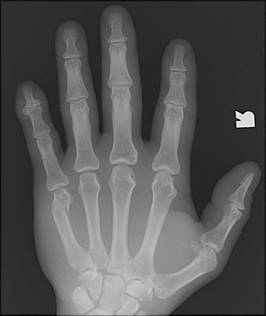

4th or 5th MCP

Bar room facture

2nd or 3rd MCP

fracture

Boxer’s fracture